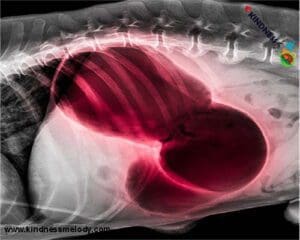

دستگاه گوارش سگ چگونه کار می کند:

در هر مرحله از سیستم گوارش ، سگ مواد غذایی را هضم و جذب می کند. یکی از ارگانهای اصلی که این کار را انجام می دهد ، روده کوچک است. روده کوچک دارای سطح بسیار وسیعی با انواع مختلف سلول ها است تا جذب مواد مغذی را تا حد ممکن موثر کند.